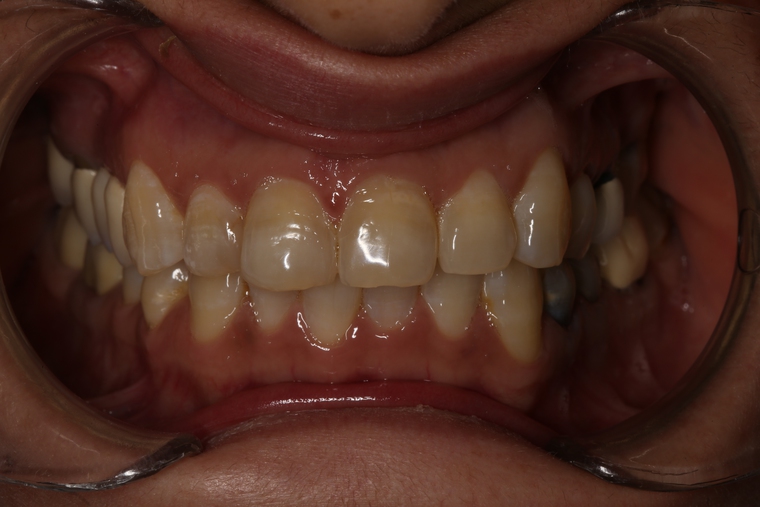

Ein Tätigkeitsschwerpunkt unserer Praxis in Salzburg ist die Implantologie. Wenn ein Zahn fehlt oder entfernt werden muss, sollte immer die Möglichkeit der Implantation im Vordergrund stehen. Ein Implantat verhält sich von den Eigenschaften genau so wie ein natürlicher Zahn. Egal ob nur ein einzelner Zahn vom Zahnarzt ersetzt werden muss oder ein ganzer Kiefer mit festsitzendem Zahnersatz versorgt werden soll, wir finden für Sie eine Möglichkeit, auch wenn die Voraussetzungen ausweglos erscheinen. Wenn möglich versorgen wir unsere Patienten mit Keramikimplantaten. Diese sind immun-neutral und können sehr oft direkt bei der Zahnextraktion eingesetzt werden. Für unsere Patienten ist daher meist nur ein operativer Eingriff notwendig!